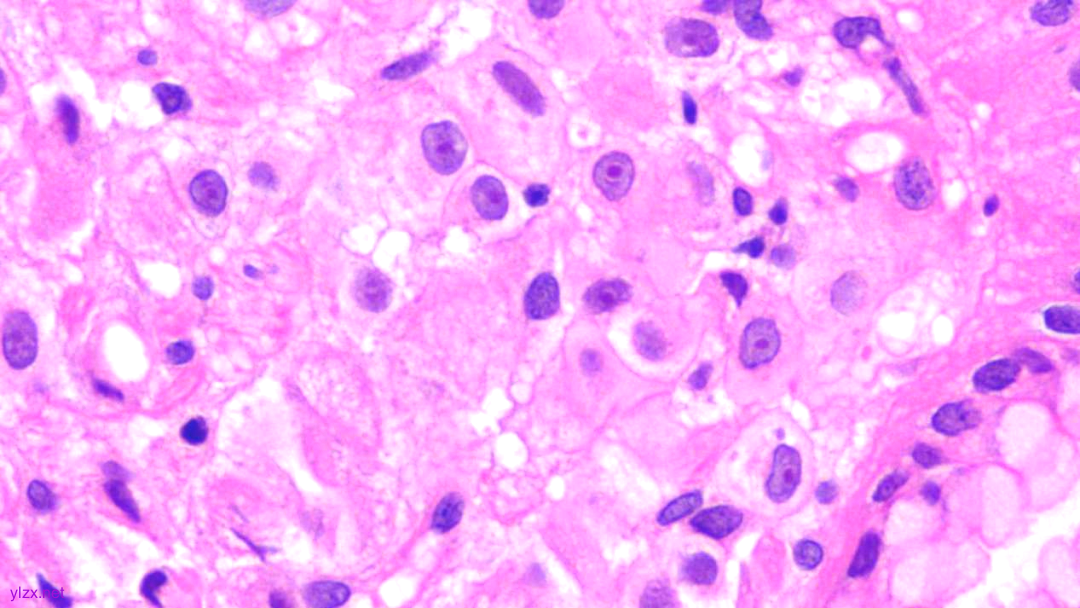

HE:

1.宫颈2点、10点:鳞状上皮下间质内见瘤组织弥漫增生,胞浆宽阔,红染,核小,较一致,部分细胞核偏位,部分细胞可见核仁;

2.宫颈5点:鳞状上皮下间质内见少量异型细胞巢,核增大,深染,浆红染,少量细胞浆内见黏液,印戒样;宫颈管搔刮组织:见血凝块、宫颈内膜组织,间质见异型细胞条索,形态同宫颈5点。

鳞状上皮下间质内见瘤组织弥漫增生,胞浆宽阔、红染,核小,较一致

瘤细胞排列偏稀疏,核小,深染,胞浆红

间质内见异型细胞巢,核增大,深染

间质内见异型细胞条索,核增大,深染,浆红

少量细胞浆内见黏液,印戒样

瘤细胞核偏位,浆红染

高倍瘤细胞见红色核仁